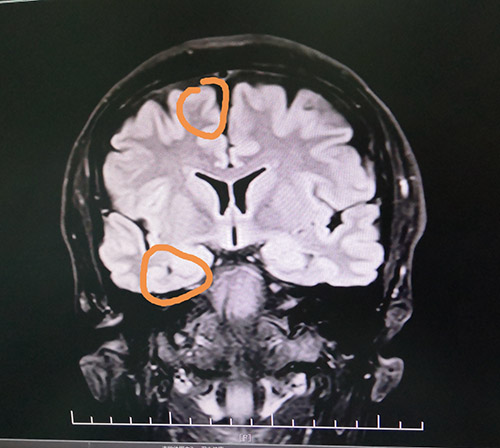

头颅海马MRS检查显示:右侧海马Cho/NAA+Cr=0.5;左侧海马Cho/NAA+Cr=0.56。PET-CT检查显示,右侧颞区FDG代谢减低。视频脑电图(VEEG)显示,在清醒状态下,额区和颞区显著,各导联较多异常波阵发出现。在睡眠状态下,颞区有少许高-极高波幅尖波、尖慢波左右不同步单发、偶波及额极、额区(右侧显著、多以睡眠期出现)。

蓝十字脑科功能神经外科主任杨忠旭博士认真查看了刘先生各项检查报告并听取相关病情汇报,认为患者脑组织结构发生病变,引起癫痫发作,经系统药物治疗无任何改善,应用现代神经影像学技术和电生理监测技术,能明确引起癫痫发作的的“责任病变”。

在征得患者家属同意后,10月28日上午,杨忠旭博士在助手杜立功及医护团队协助下为刘先生进行了“癫痫病灶切除术”手术。由于患者患有高血压、脑萎缩,脑血管异常脆弱,且局部脑组织结构异常,多处异常放电部位,为手术带来挑战,手术中需要格外小心。在全程脑电监测下,杨博士处之泰然,游刃有余,在助手密切配合下,为患者切除了颞叶、海马和额叶病灶。癫痫病灶切除后,再次监测脑区,无异常放电,手术成功。紧接着彻底止血,严密缝合硬脑膜,复位骨板……紧张的手术终于结束。